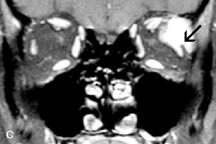

Lacrimal Gland Tumors

Lacrimal gland lesions present special problems in diagnosis and management. Pleomorphic adenoma (benign mixed tumor) should not be biopsied, but rather excised in toto. On the other hand, for lymphoma and inflammatory infiltrates, incisional biopsy is more appropriate than complete excision of the lacrimal gland. Thus, preoperative clinical and radiologic evaluation are especially crucial in planning appropriate surgical management.

Pleomorphic adenomas demonstrate long T1 and T2 signal characteristics. They may show heterogeneity on T2-weighted images74 and moderate to marked enhancement with contrast.75 Signal characteristics of adenoid cystic carcinoma include hypointensity to fat on T1-weighted images, hyperintensity to fat with increased T2 weighting, and isointensity to fat on proton density-weighted studies (Fig. 23).31,75 Secondary bony alterations of the lacrimal fossa associated with lacrimal gland tumors, such as remodeling (benign mixed tumor) or destruction (adenoid cystic carcinoma), are seen indirectly on MR images; however, bone windows on CT scans provide better delineation of these changes. In contrast to the round or globular appearance of benign or malignant epithelial tumors of the lacrimal gland, lymphoproliferative tumors usually appear to be molding or draping onto the globe and the surrounding bony orbit.

Fig. 23. A. T2-weighted and (B and C) postcontrast fat-suppressed T1-weighted MR scans demonstrate an infiltrative lacrimal region mass than invades the lateral rectus muscle (arrows). This highly cellular lesion is seen to have a very hypointense appearance on the T2-weighted scan.